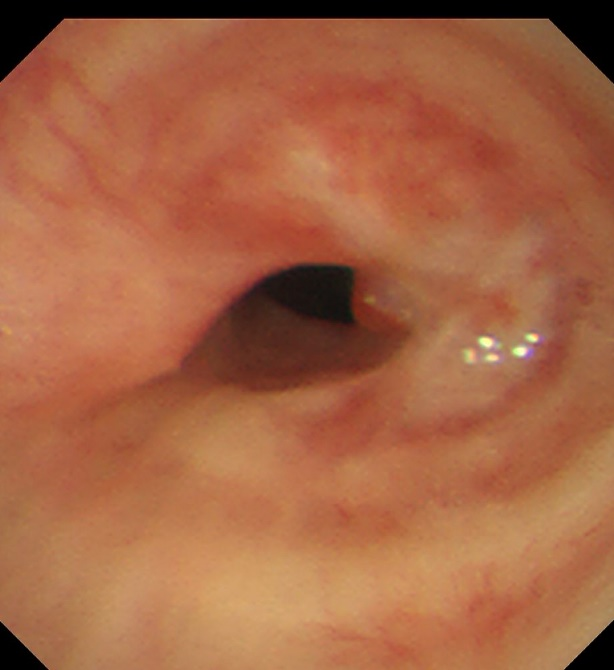

患者,女,50岁,因“外伤后呼吸困难2月”来到av线上 全科医学科治疗。患者2月前因外伤致气管撕裂,在当地医院行气管修补术,术后出现进行性加重呼吸困难。患者来到我院住院后,稍微活动就会感到气促,已不能活动,肺功能显示重度阻塞性肺通气功能障碍,胸部CT显示气管下段重度狭窄,支气管镜检查显示气管下段距隆突2cm处重度瘢痕狭窄,最窄处仅4mm,随时都会发生窒息甚至猝死,手术迫在眉睫!

气管下段狭窄激光治疗+Y型硅酮支架植入后

术后患者呼吸困难等症状得到了立竿见影的缓解,术后第二天复查支气管镜可见支架在位良好,管腔通畅。大大改善了患者的生活质量,患者于术后第三天下午顺利出院。